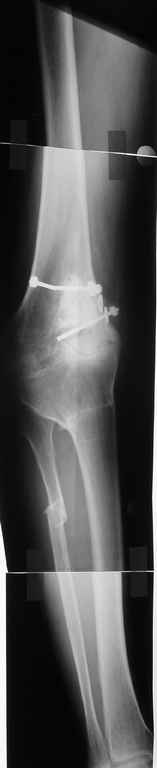

Пациент 59 лет, в 1982 году по поводу остеобластокластомы была выполнена частичная резекция проксимального отдела бедра с пластикой дефекта костно-хрящевым трансплантатом (моноблок)с фиксацией металлическими стяжками. В последующем по поводу деформирующего артроза выполнена корригирущая остеотомия большеберцовой кости. Исход представлен на рентгенограмме. В настоящий момент пациента беспокоят боли в коленном суставе, деформация, и ограничение движений. Варусная деформация коленного сустава 20, движения сгибание 115, разгибание 150, ходит с тростью, выраженная хромота, работа не связана с физическими нагрузками. Правый коленный сустав без патологии. Уважаемые коллеги просим высказать своё мнение - артродез коленного сустава или эндопротезирование.